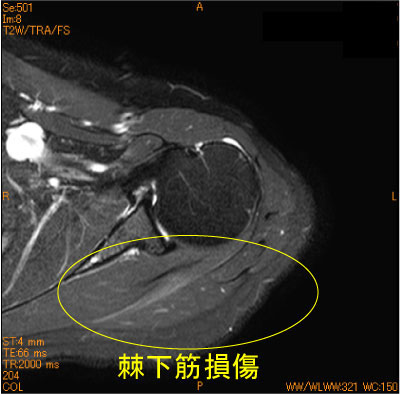

30代女性、バレーのレッスンで腕を内外旋すると疼痛出現。

棘下筋に筋挫傷を認めている。腱板断裂疑いであったが、腱板ばかり見ていると見落とす。

脂肪抑制T2WI は必ず必要である。

![]() Axial T2WI 脂肪抑制 |